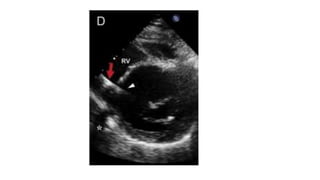

Pseudoflow